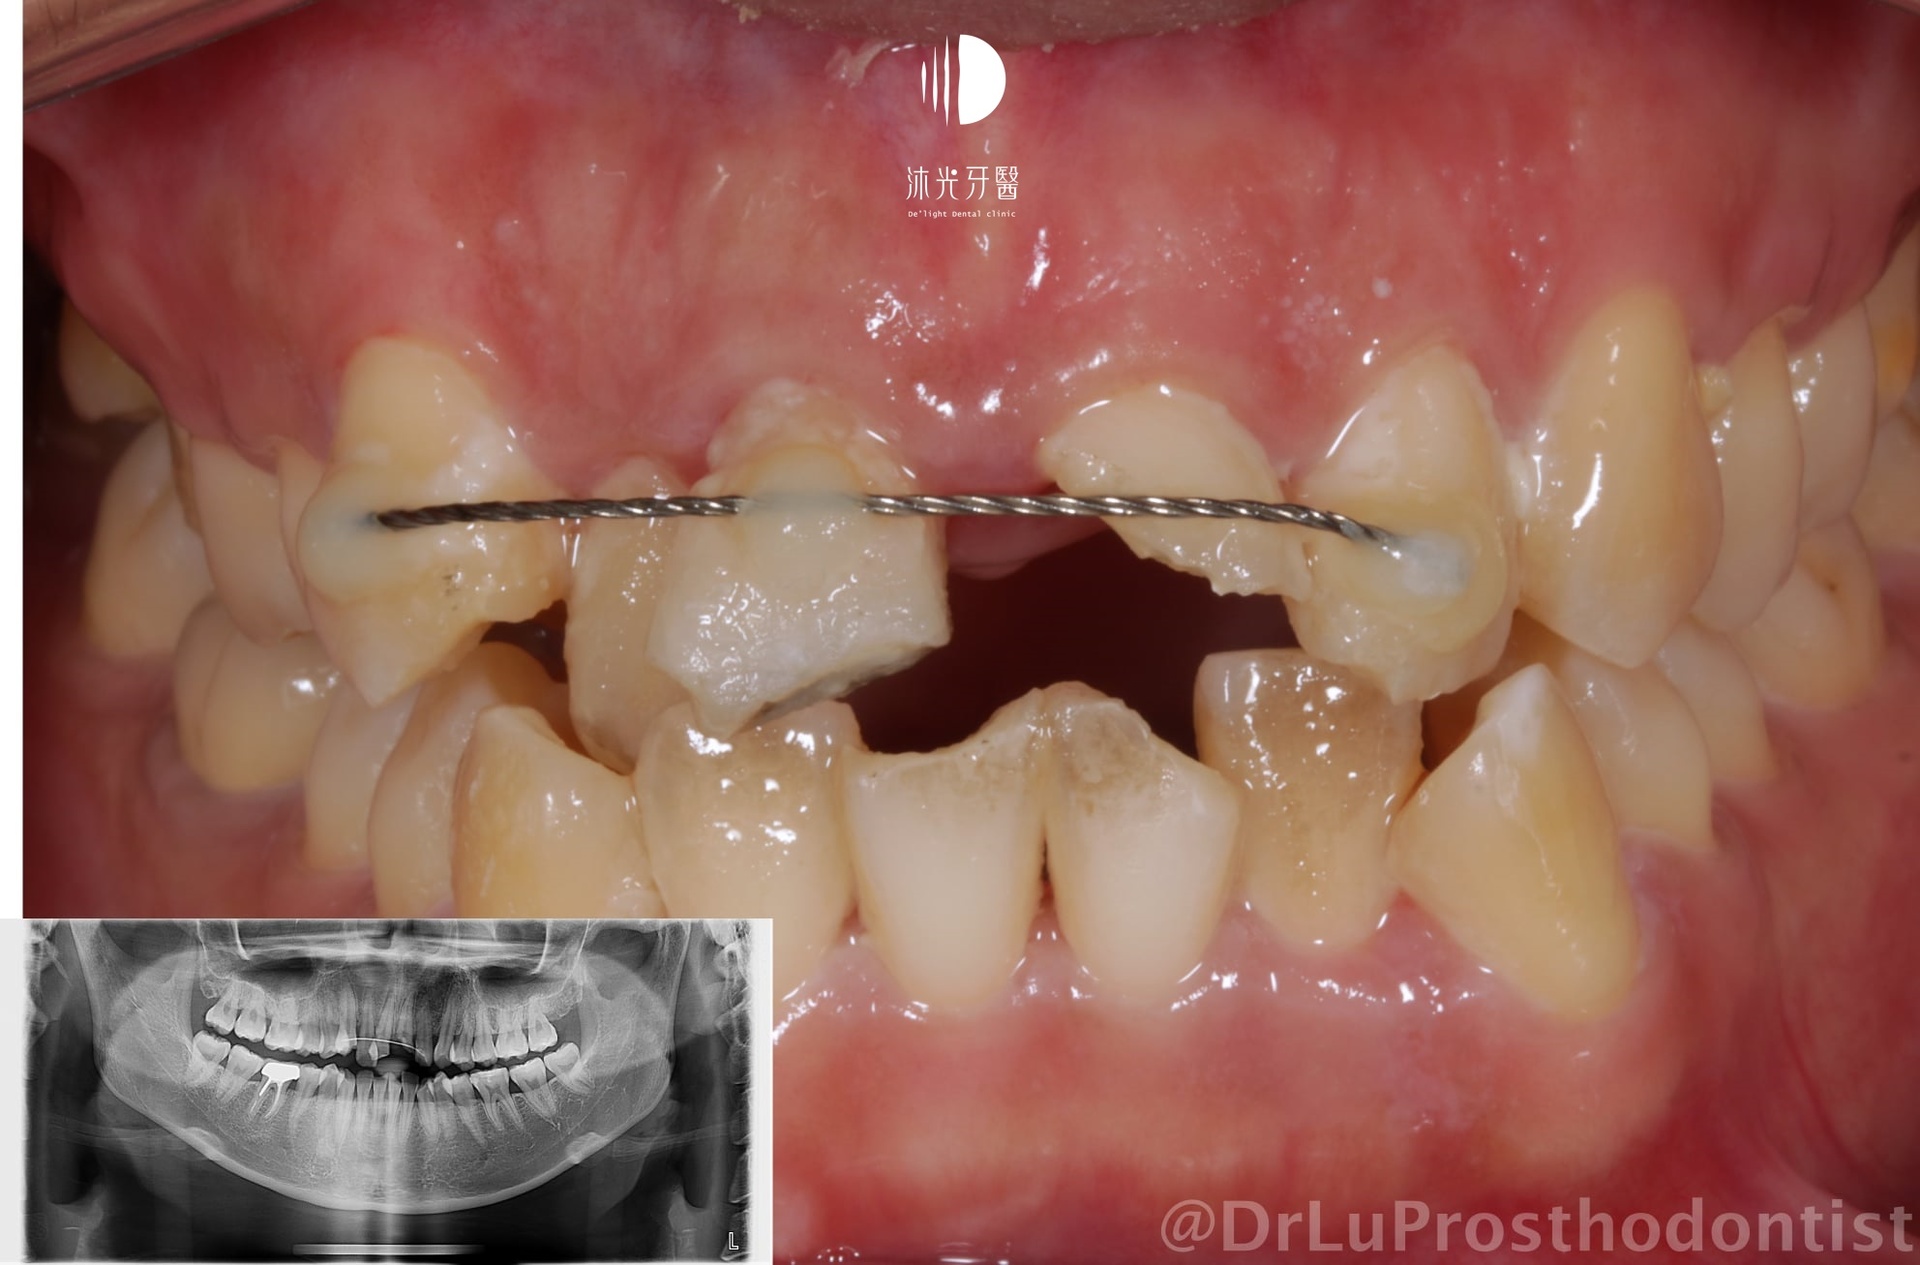

今天要分享的案例是位車禍患者的前牙重建,幸好沒有嚴重的齒槽骨損傷讓整個治療並沒有經過太多的手術過程。

矯正治療完成後才安排縱裂的左側門牙拔牙、補骨、植牙等流程;可以看到即使門牙植牙區水平方向的組織量不足,但在條件良好的情況下單單透過植牙臨時假牙的形態去塑型周圍牙肉,還是可以達到正面觀時不錯的結果,達到患者希望減少手術次數的要求。